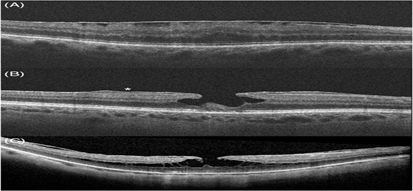

Hình ảnh trên OCT của màng trước võng mạc và các khái niệm có liên quan: A- màng trước võng mạc, B- lỗ lớp hoàng điểm cùng với tăng sinh trước võng mạc (dấu sao), C- tách lớp VM